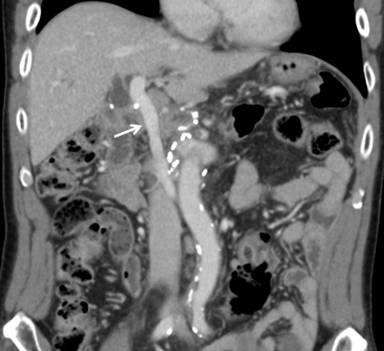

The patient returned to an oral diet on the 4th postoperative day. The postoperative course was uneventful and the patient was discharged on day 14 in generally good condition. The permanent pathologic report revealed an invasive mucinous cystadenocarcinoma with invasion to the common bile duct wall and peripancreatic soft tissue with regional lymph node metastasis (metastasis of 5 lymph nodes out of the 55 lymph nodes harvested) (Figure 3). He received UFT (tegafur) plus gemcitabine combination adjuvant chemotherapy and he is still alive. A follow-up CT at the 31st postoperative month showed a patent graft and no evidence of recurrence (Figure 4).

Figure 4. A follow-up CT at the 31st postoperative month showed a patent graft (arrow) and no evidence of recurrence. |